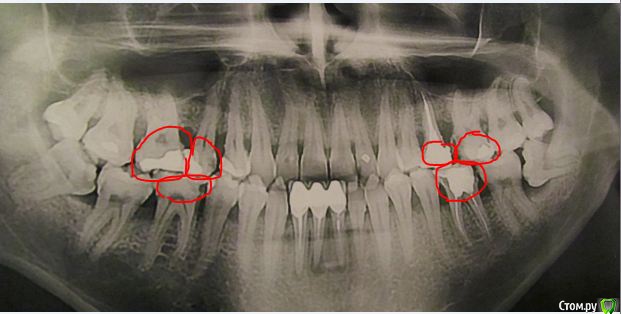

paradontit Опубликовано 12 ноября, 2016 Поделиться Опубликовано 12 ноября, 2016 Снимок в 2013 годуСнимок в этом году, лечения не было никакогоДорогие парадонтологи, посоветуйте метод лечегия в данной ситуации. Очень интересуют независимые мнения. Ссылка на комментарий

___49___ Опубликовано 14 ноября, 2016 Поделиться Опубликовано 14 ноября, 2016 Ваши нижние 8 ки не встанут в правильную позицию, неверное положение с упором в соседние зубы + их основной рост уже прекратился, между 8ками и 7ками сформирован карман который не возможно прочистить (принцип бутылки) - это приводит к возникновению кариеса (47 зуб уже необходимо осматривать по дистальной стенке ) или воспалению . Удаляйте. 1 Ссылка на комментарий

St. Опубликовано 14 ноября, 2016 Поделиться Опубликовано 14 ноября, 2016 Плюс к выше описанным рекомендациям обратите внимание на нижние центральные зубы под коронками. На них идет хроническое воспаление на корнях вследствие не идеально пролеченых каналов 2 Ссылка на комментарий

St. Опубликовано 15 ноября, 2016 Поделиться Опубликовано 15 ноября, 2016 Я, к сожалению, не узнал, в каких зубах у меня залипухи (кроме зубов под коронкой). На первый взгляд, как минимум эти. Ссылка на комментарий